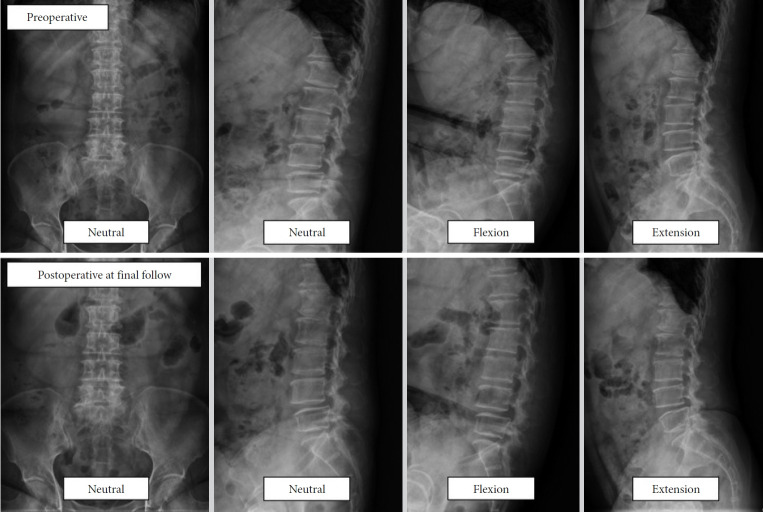

目的:本研究旨在评估采用双门静脉内镜脊柱手术(BESS)单侧椎板切开术进行双侧减压(ULBD)的临床和影像学结果,以治疗伴有或不伴有低级别退行性腰椎滑脱(DLS)的中央管狭窄患者。方法:对170例2015 - 2018年间行BESS-ULBD的患者进行回顾性观察研究,随访至少2年。将患者分为中枢性狭窄合并低度DLS的A组(68例)和单纯中枢性狭窄的B组(102例)。临床结果采用视觉模拟量表(VAS)评估背部和腿部疼痛、Oswestry残疾指数(ODI)和改良MacNab标准。放射学评估包括动态屈伸x线片矢状面平移测量。结果:两组在最终随访时均显著改善了临床结果(结论:BESS-ULBD是一种安全有效的微创治疗中央管狭窄的选择,无论有无低级别DLS。该技术可有效缓解症状,保持脊柱稳定性,并为精心挑选的患者提供了一种有希望的替代更具侵入性的融合手术。

Methods: A retrospective observational study was conducted on 170 patients who underwent BESS-ULBD between 2015 and 2018, with at least 2 years of follow-up. Patients were categorized into 2 groups: group A (68 patients) with central stenosis and low-grade DLS and group B (102 patients) with central stenosis alone. Clinical outcomes were assessed using the visual analogue scale (VAS) for back and leg pain, Oswestry Disability Index (ODI), and Modified MacNab criteria. Radiological assessments included sagittal translation measurements on dynamic flexion-extension radiographs.

Results: Both groups significantly improved clinical outcomes at the final follow-up (p<0.05). Group A's mean VAS scores improved from 3.8±2.4 to 1.9±2.0 for back pain and from 6.4±1.8 to 2.3±2.0 for leg pain. In group B, back pain improved from 3.9±2.5 to 1.7±1.9, and leg pain from 6.6±2.0 to 2.2±2.2. ODI scores also improved significantly in both groups. Radiological evaluation showed no significant changes in sagittal translation postoperatively, indicating preserved spinal stability. Both groups had comparable clinical outcomes, with no major complications reported.

Conclusion: BESS-ULBD is a safe and effective minimally invasive option for managing central canal stenosis, with or without low-grade DLS. This technique provides substantial symptom relief, preserves spinal stability, and presents a promising alternative to more invasive fusion procedures in carefully selected patients.